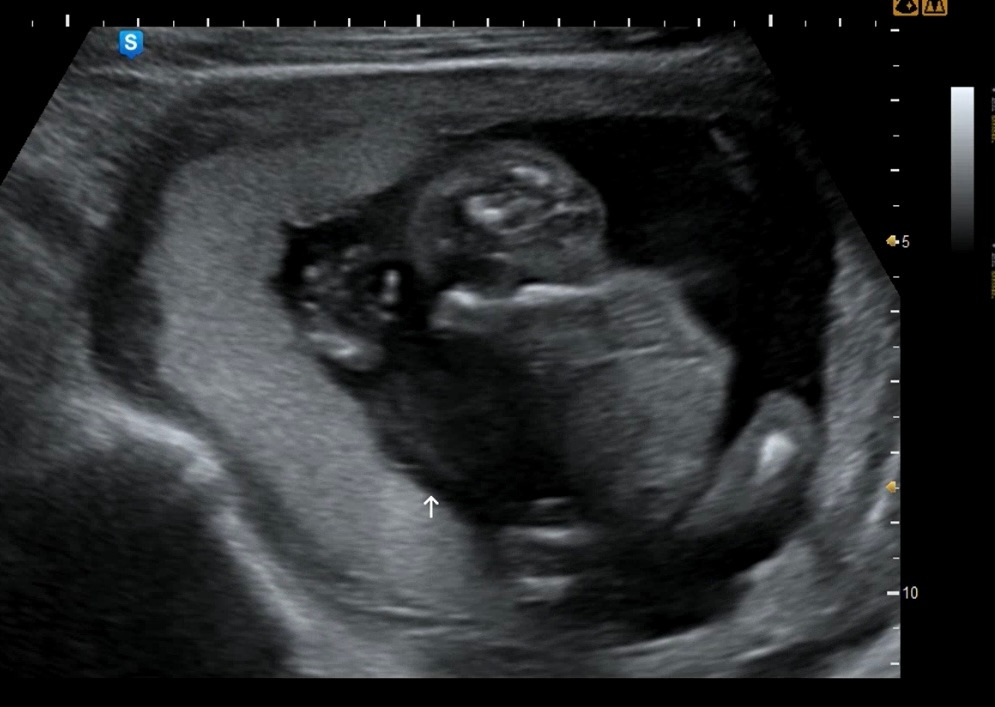

12주차: 조금 커서 꽤 인간처럼 되어버린 빵빵이

16주차 ㅋㅋㅋ 애기가 좁은지 몸부림을 치고 있다. 너무 귀여워!!!!!! 머리에 두개 점은 눈 아니고 아마 뇌일 텐데.. 꼭 눈같아서 더 웃기다(눈 맞나? ㅋㅋㅋ)